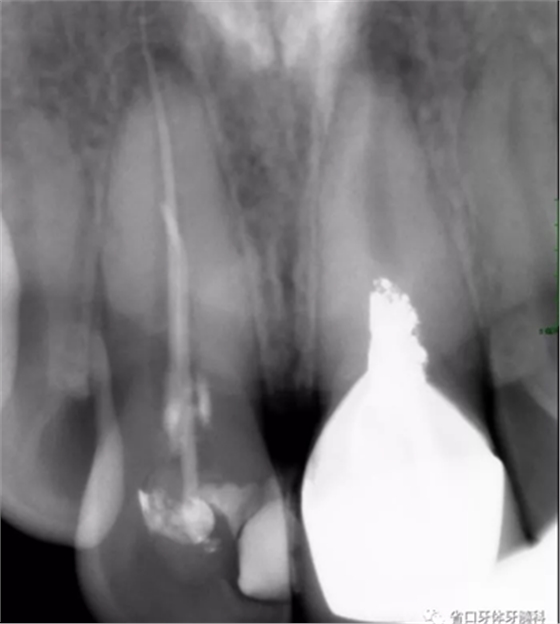

X線檢查:11冠部近中鄰面見高密度充填影像,邊緣有低密度線形暗影,根管內(nèi)見高密度稀疏影像,根管內(nèi)充填物與根管壁不密合,超出根尖孔約4-5mm,根尖周見低密度暗影;21根管上段修復體高密度影像,中下段根管空虛,根尖周見低密度暗影。圖3

圖3 治療前X線片